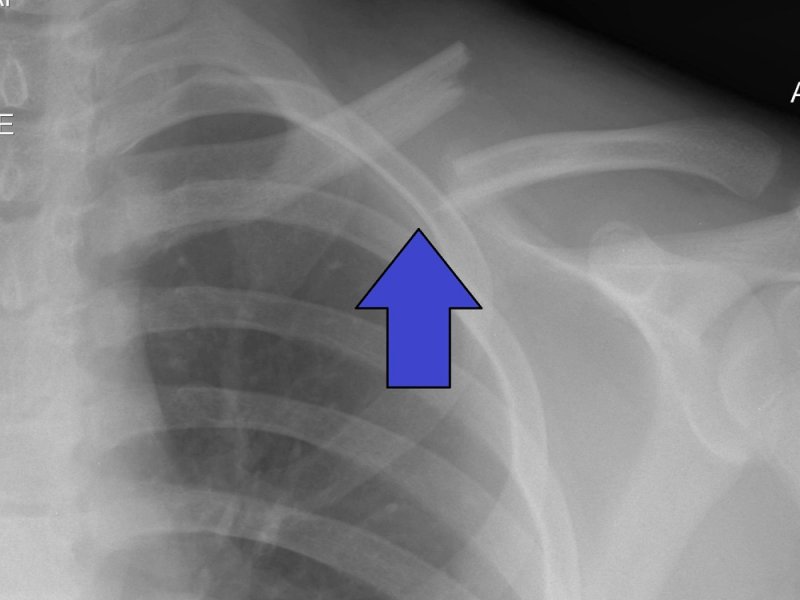

Новое исследование, представленное в Journal of the Endocrine Society, показало насколько эффективным может быть искусственный интеллект (ИИ) в чтении электронных радиологических снимков. В частности, система смогла лучше врача определить пациентов с переломами, у которых присутствует риск остеопороза.

Инструменту ИИ дали название XRAIT. По сравнению с ручной диагностикой, было идентифицировано в пять раз больше серьезных переломов у пациентов.

«XRAIT может предложить помощь системе здравоохранения, ограниченной определенными ресурсами. Это позволит оптимизировать работу с пациентами, которые находятся в рисковой группе. XRAIT нет необходимости использовать для первичной диагностики», - рассказывает один из исследователей, глава Лаборатории клинических исследований и эпидемиологии в Институте медицинских исследований Гарвана в Сиднее, Австралия, Жаклин Сентер.